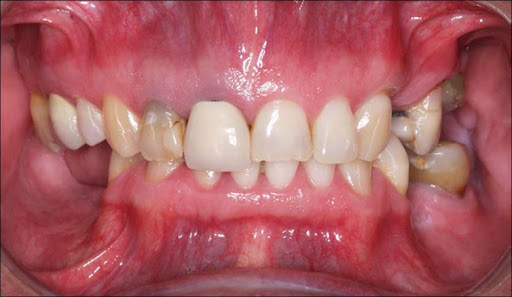

Vestibular or neurologic pathologies, use of prescription drugs or psychotropic substances. The patients have been divided into two groups: 36 adult patients with normal occlusion (good alignment, 1st class or mild 2nd class deep bite for mandibular retrusion) constituted the group A, while 30 adult patients with previous whiplash and malocclusion (cross bite, mandibular shift, bad alignment, edentulous spaces) constituted the group B. To simulate the conditions of sleep (with a reduction of proprio- and esteroceptive inputs for postural management performed by CNS), we used the postural Romberg analysis (feet together, closed eyes) on a stabilometric platform changing occlusal parameters only, under the following conditions: